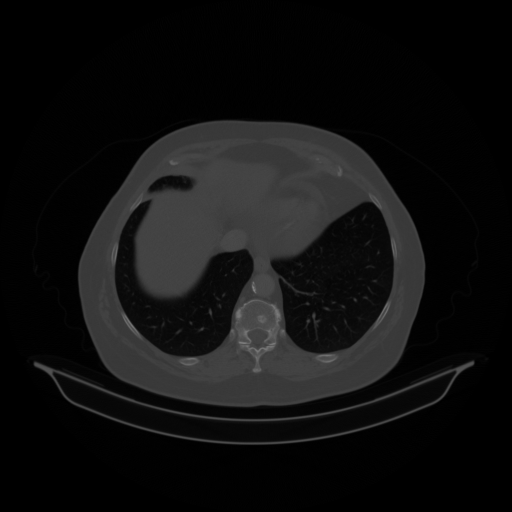

Generated VENOUS CT scan (A→B translation)

Full window (WL 1023.5, WW 4095 β†’ Low βˆ’1024, High +3071)

Lung window (WL -600, WW 1500 β†’ Low βˆ’1350, High +150)

Mediastinum window (WL 40, WW 400 β†’ Low βˆ’160, High +240)